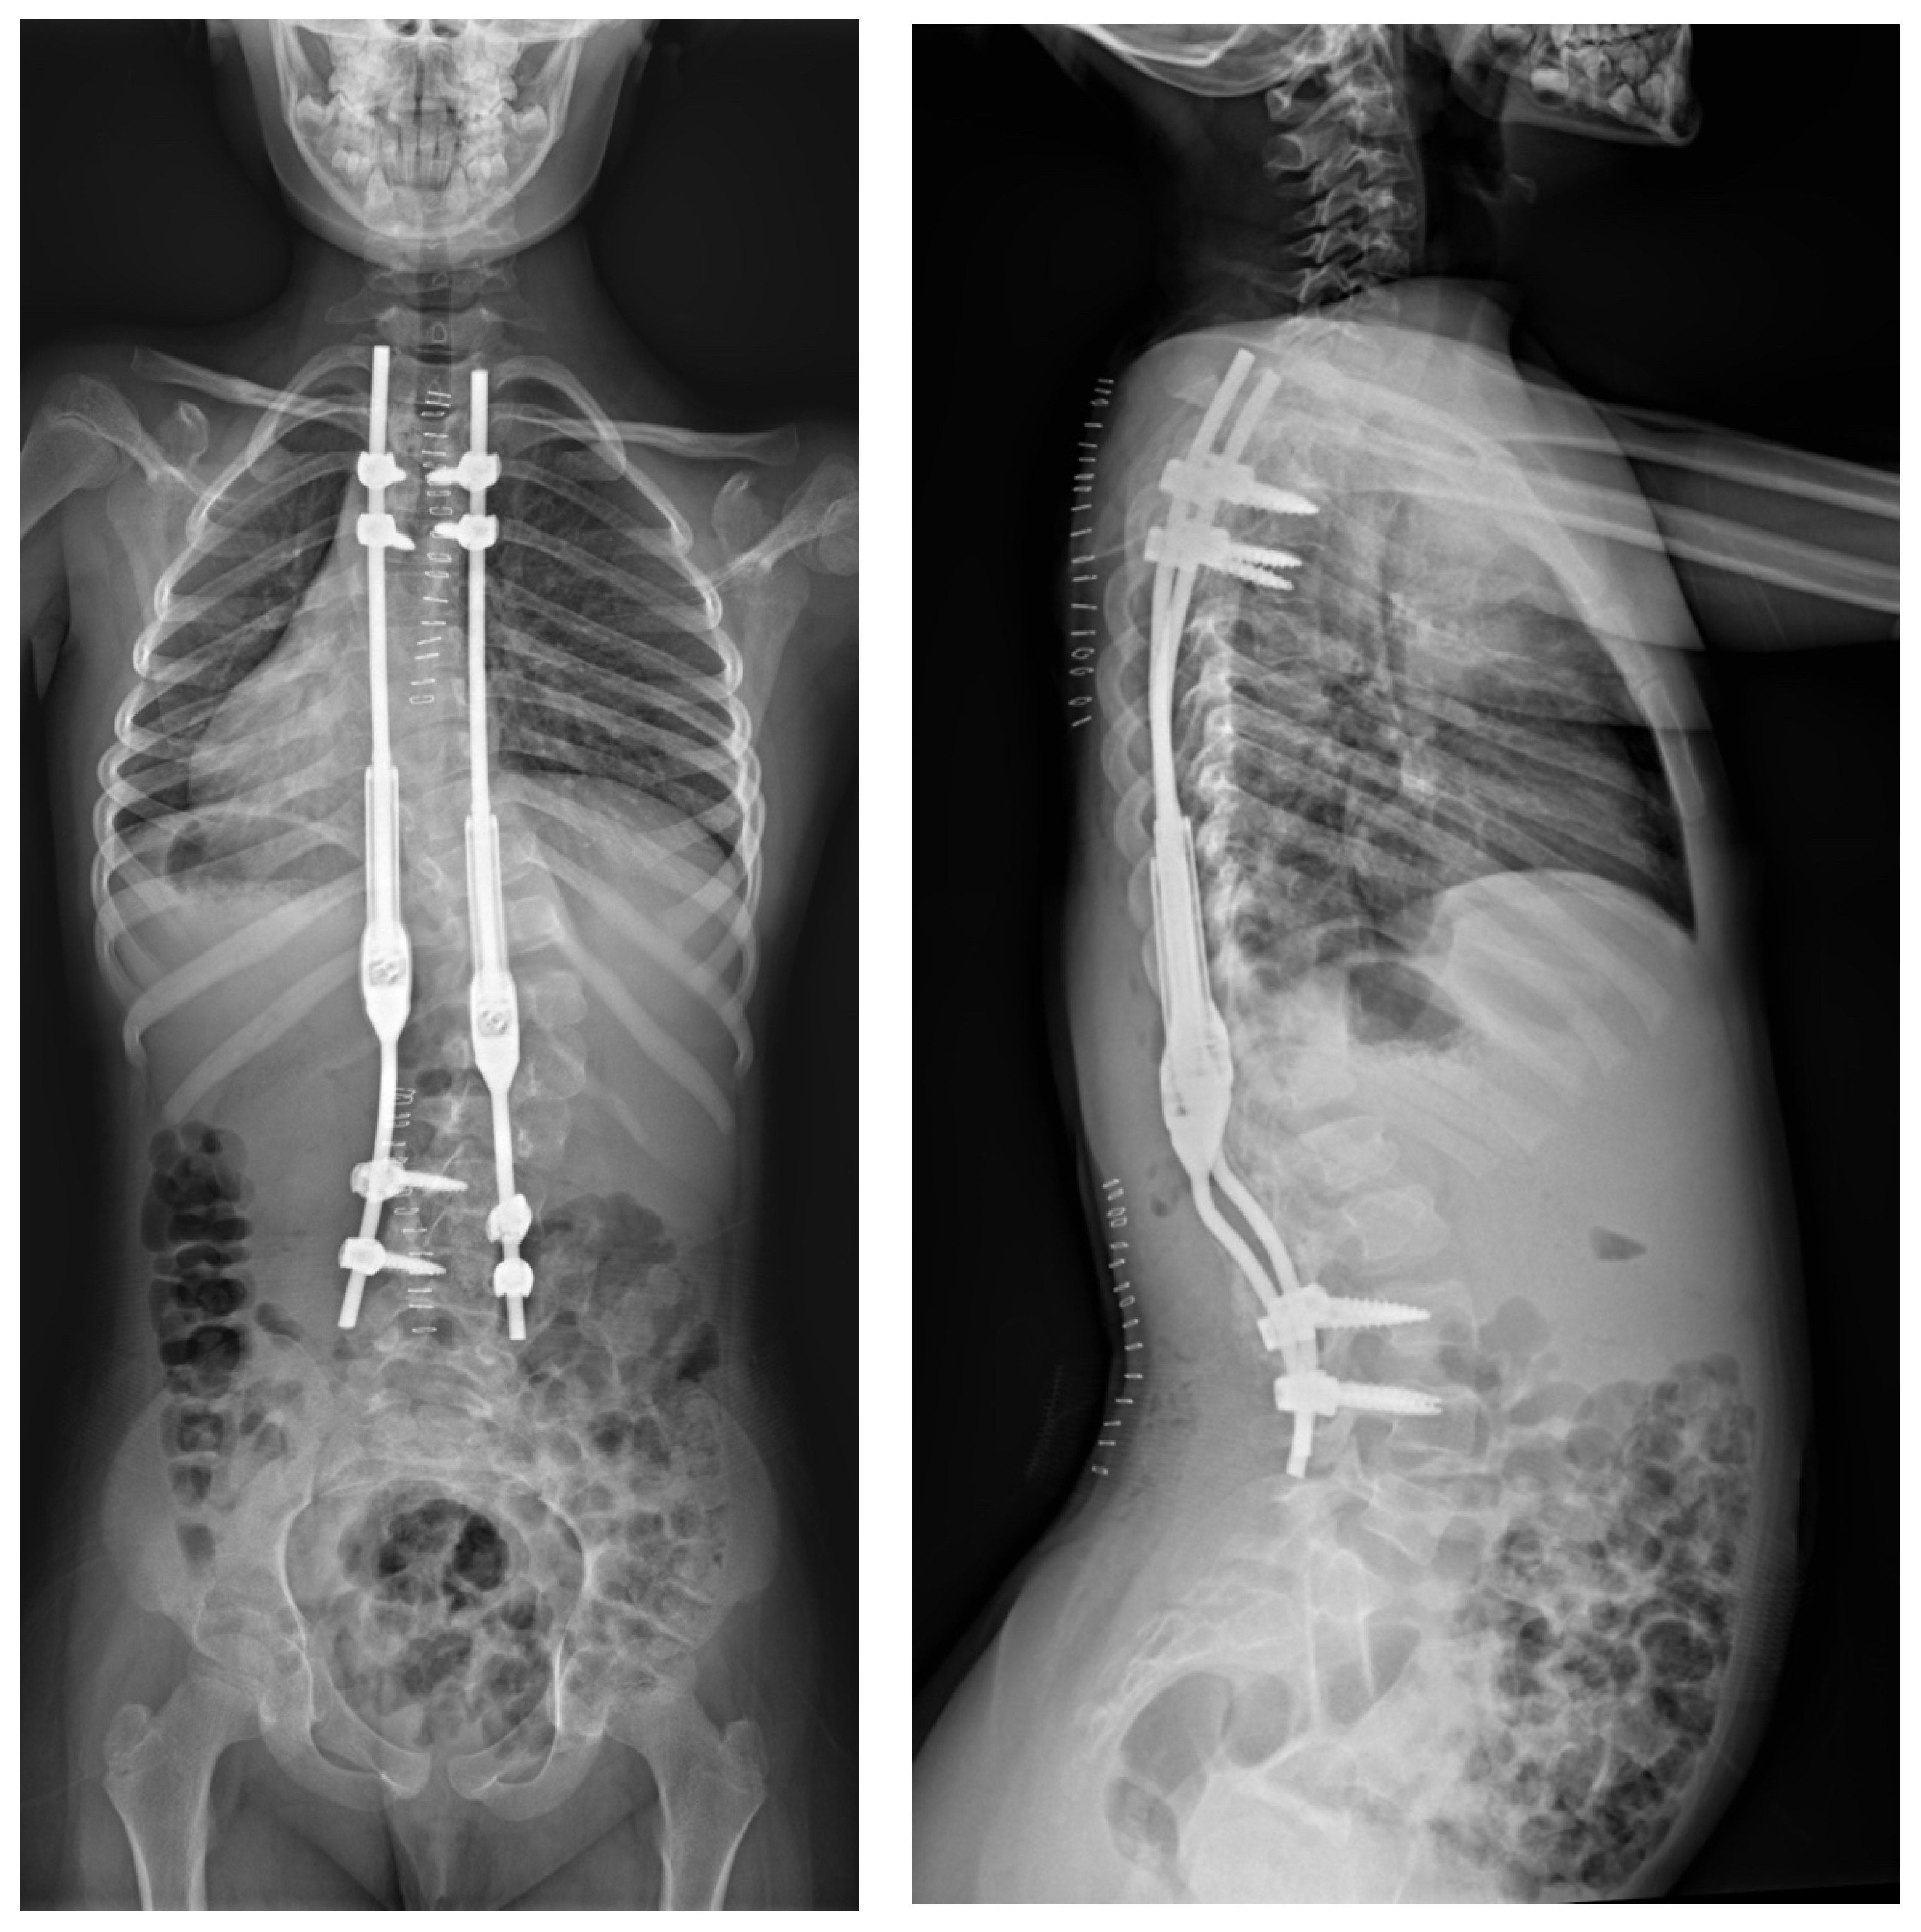

2.3. Example of Congenital Kyphosis